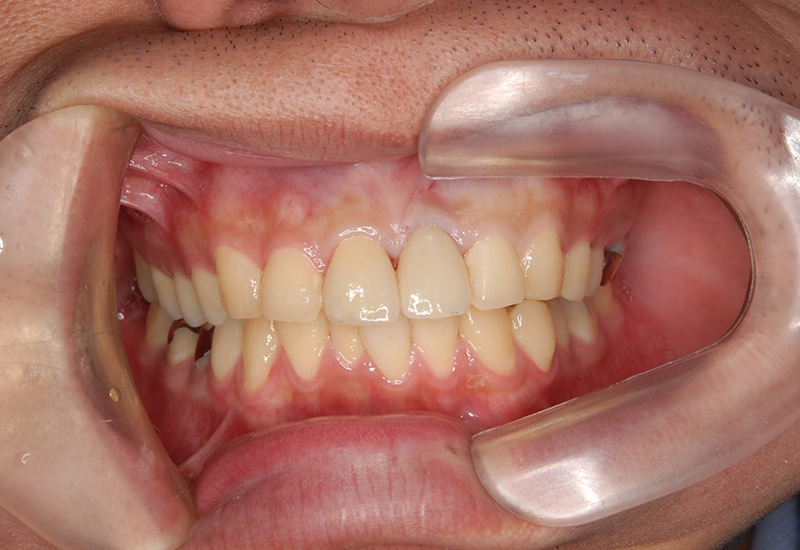

治療前後の写真

治療前 |

治療後 |

治療前

治療後